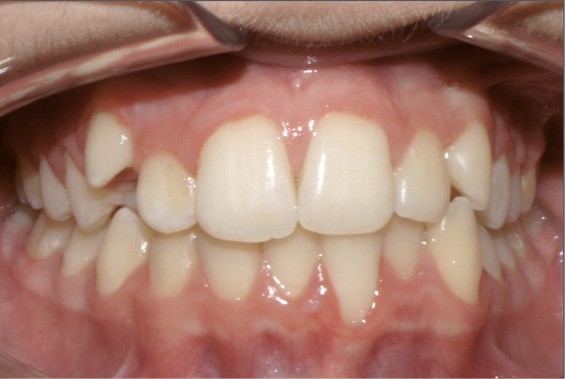

Examen endo-buccal (fig. 2a-e)

L’examen intra-arcade montre une hygiène correcte, un parodonte fin, non inflammatoire avec absence de gencive attachée en regard de 13, 33 et 31. On observe même une récession gingivale en regard de 31.

Dans le sens transversal, l’occlusion des secteurs latéraux est correcte mais on constate une discordance des médianes incisives liée à la déviation de la médiane maxillaire vers la droite et à celle de la médiane incisive mandibulaire vers la gauche.